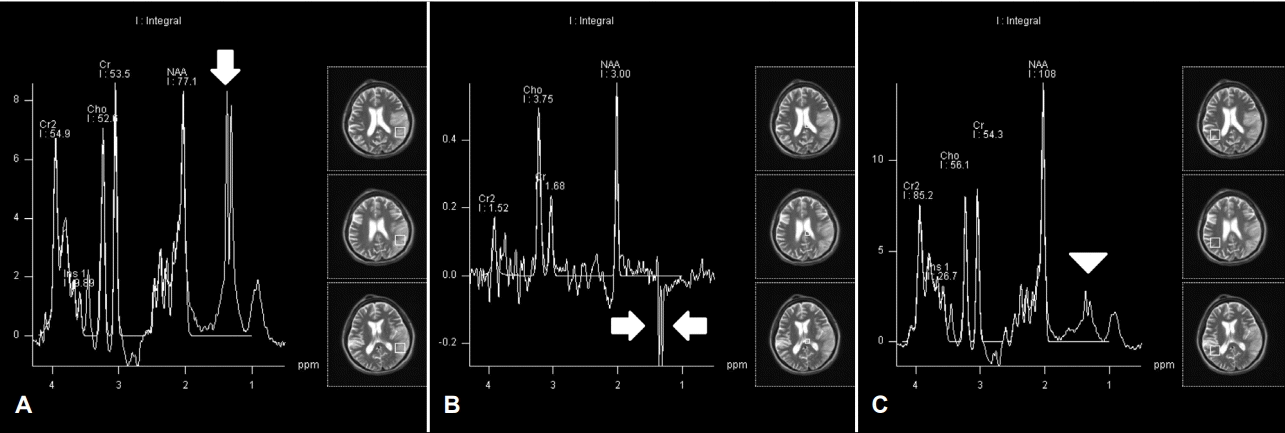

Figure 2.

(A) MR spectroscopy images obtained from the left temporal lobe show an increased lactate peak (1.3 ppm) at short TE (30 msec) (B) with a characteristic inverted double peak on long TE (135 msec) image (arrows). (C) MR spectroscopy (short TE, 30 msec) image obtained from the normal appearing region at the right temporal lobe show a mildly elevated lactate peak (arrowhead). MR; magnetic resonance, TE; echo times, NAA; N-Acetylaspartate.